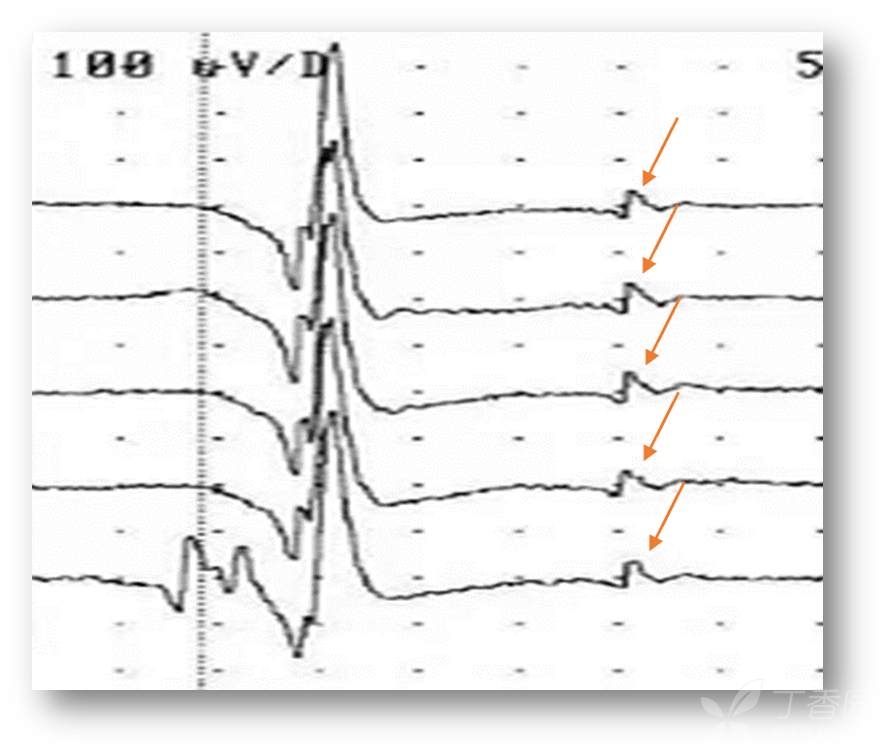

图5 卫星电位(SP)参考图

图6 卫星电位(箭头)

1、短时独立,与MUP主波具有锁时关系;

2、卫星电位出现率(含卫星电位的运动单位个数/运动单位个数)>10%;

3、卫星电位早期即可出现,也不会随诊病程延长而逐渐增多或减少,提示MSA患者的卫星电位是一种慢性神经源性损害后再生不良的电生理反应。